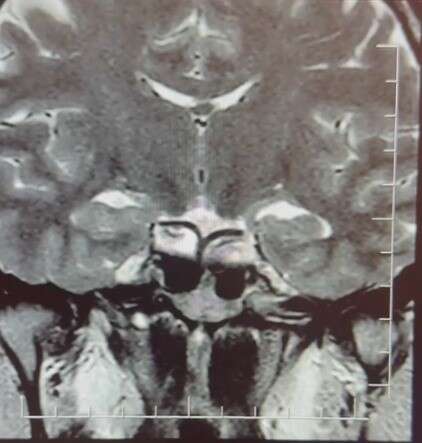

Yapılan ileri tetkiklerde hastaya hipofiz MR çekildiğini aktaran Çiftçoğlu, "MR sonucunda beynin hipofiz bölgesinde ‘prolaktinoma’ olarak adlandırılan bir tümör tespit ettik. Bu tümör, prolaktin hormonunun aşırı salgılanmasına neden oluyor. Genellikle iyi huylu olup ilaç tedavisiyle kontrol altına alınabiliyor" diye konuştu.

Gebelik belirtilerine benzer şikayetlerin farklı hastalıkların habercisi olabileceğine dikkat çeken Çiftçoğlu, "Prolaktin hormonu aslında beyinde hipofiz bezinden salgılanan ve süt salınımını sağlayan hormondur. Bunun yüksek olduğunu tespit ettikten sonra hastada hipofiz MR çektirdik. Çektiğimiz beyin MR'ında hastanın hipofiz dediğimiz bölgede kitleyi tümörü tespit ettik. Prolaktinoma dediğimiz bir tümör. Prolaktinoma tümörü beyinde hipofiz bölgesinde bulunmakta olup prolaktin hormonunun aşırı miktarda salgılanmasını sağlayan bir tümördür. Bu durumda iyi huyludur, kanserleşme olmasını çok yoktur. Dolayısıyla ilaçla tedavisi mümkündür ama gebelik şikayetlerini de andırdığı için mutlaka ayırıcı tanıda akılda tutulması gereken bir durumdur. Hasta da bizle öğrendi 'hamileyim' diye geldi hasta, gebelik muayenesi olma talebiyle geldi ancak biz tümörü tespit ettik. Önce gebe olmadığını tespit ettik ve sonra 'Bu şikayetlere sebep olabilecek ne var?' diye araştırdığımızda bu durum ortaya çıktı. Yani tümörü de aynı gün içerisinde değil birkaç gün sonra ileri tetkik sayesinde öğrenmiş oldu" dedi.